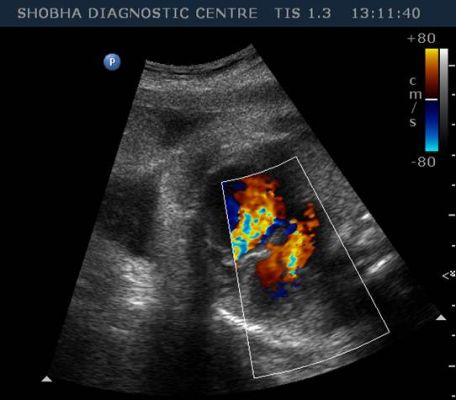

Fetal Echocardiography

WE ROUTINELY DO FETAL ECHOCARDIGRAPHY AT OUR CENTRE

- Latest equipment with 3D/ 4D facility